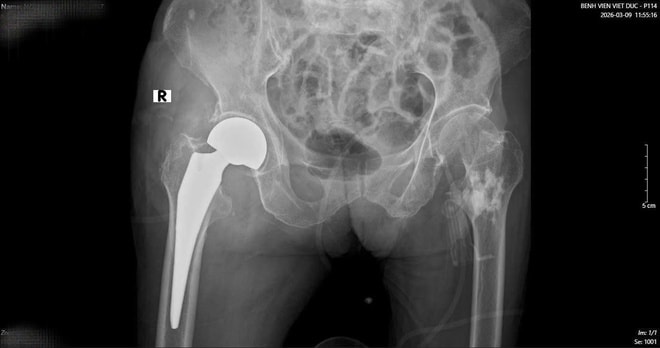

Sau một tuần, khi các chỉ số sức khỏe ổn định, cụ bà tiếp tục bước vào cuộc đại phẫu thứ hai. TS.BS Hoàng Ngọc Sơn đã trực tiếp phẫu thuật thay khớp háng cho cụ. Nhờ sự chuẩn bị kỹ lưỡng của đội ngũ y bác sĩ, ca mổ đã thành công tốt đẹp.

Chỉ sau một tuần thay khớp, cụ bà đã có thể tập đi và vận động gần như bình thường. Đây là kết quả rất khả quan đối với một bệnh nhân cao tuổi vừa trải qua hai cuộc đại phẫu liên tiếp trong vòng 16 ngày.